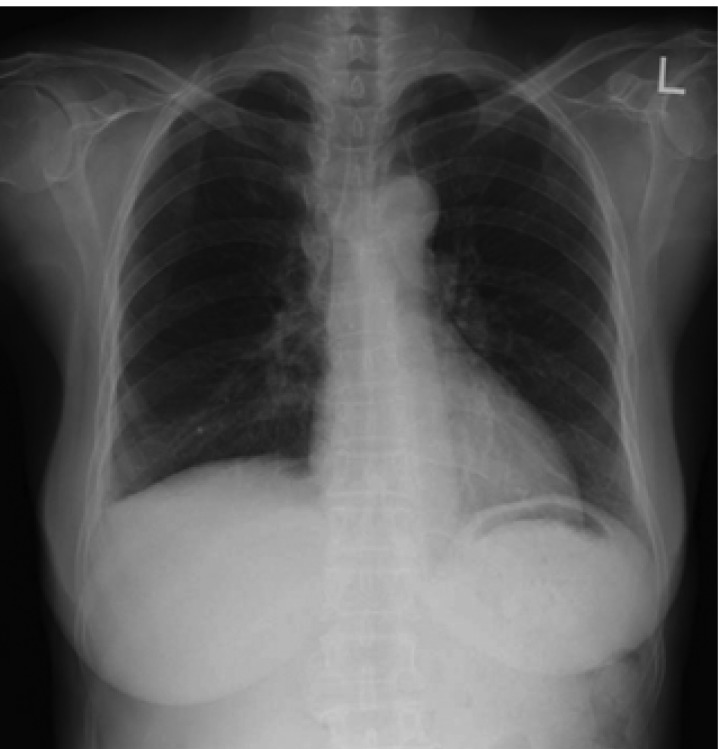

Laboratory data on admission were within normal limits. A chest X-ray (Figure 1A) and CT scan (Figure 1B) showed massive right pleural effusion, and ultrasonography, CT and MRI scans revealed a 6×10×12 cm in sized intrapelvic huge solid mass, including cystic components involving both adnexae and the uterus, and a moderate amount of intra-abdominal fluid collection (Figure 2, 3). The MRI and CT scans showed no evidence of a metastatic disease involving the lymph nodes, bone or abdominal organs. The serum CA125 concentration was 82.49 U/mL (normal, 0~35 U/mL). The serum levels of carcinoembrionic antigen (CEA) and carbohydrate antigen 19-9 (CA19-9) were normal. A cytological examination of both the ascites and pleural fluid showed no signs of malignant cells. An explorative laparotomy was performed based on the suspicion of ovarian cancer. Serous ascites, a moderately enlarged uterus and a large right ovarian mass were found, but there were no signs of metastatic spread. A total abdominal hysterectomy (TAH) was performed, with a bilateral salpingo-oophorectomy (BSO), partial omentectomy and pelvic lymph nodes sampling. During the operation, the ovarian tumor ruptured in the pelvic cavity and 2,500 mL of serous ascites were drained during the laparotomy. Due to the right pleural effusion, a trocar tube was inserted into the right thorax, with a total of 650 ml of serous fluid collected.

Figure 1

(A) Chest X-ray film showing right pleural effusion (arrows). (B) Contrast enhanced CT scan showing large amount of pleural effusion (arrow)